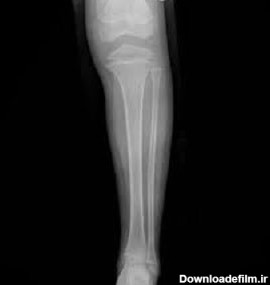

عکس ساق پای سالم

عکس رادیولوژی ساق پای سالم

تکنیک های رادیوگرافی ساق پا